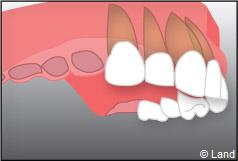

– le remplacement d’une dent unitaire. Grâce à ce procédé, il n’y a pas de mutilation des dents voisines.

– le remplacement de plusieurs dents manquantes par un bridge sur implants. Cela évite l’appareil amovible.